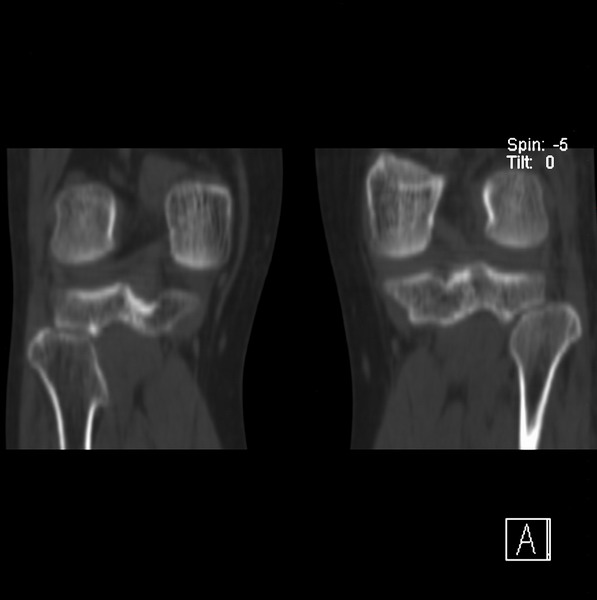

标题: CT21917:右腓骨小头是否骨软骨瘤? [打印本页]

标题: CT21917:右腓骨小头是否骨软骨瘤?

女、43.

不是骨软骨瘤,“牵拽征”,正常变异。有平片吗?

正常变异,“牵拽征”,比目鱼肌牵拽.

比目鱼肌附着点